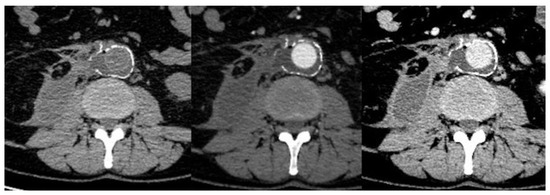

3.2. Computed Tomography (CT)—CT–Angiography (CTA)